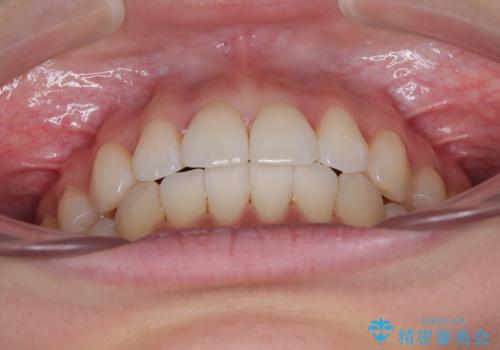

1. 開始前

3. 終了時

1. 抜歯矯正の軽度後戻りを解消 インビザライン矯正の治療前

3. 抜歯矯正の軽度後戻りを解消 インビザライン矯正の治療後